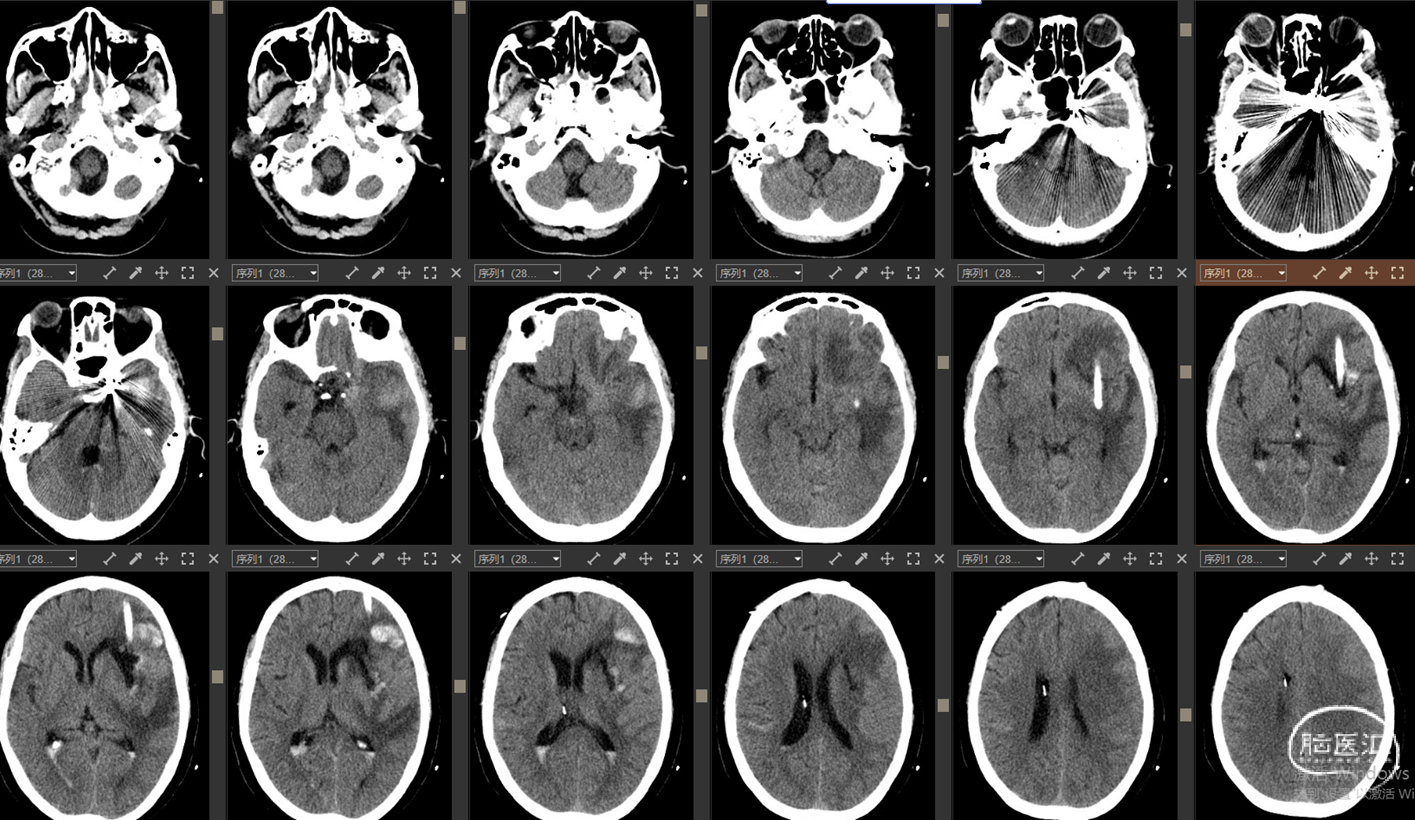

现病史:12小时前无明显诱因突发出现右侧肢体无力,伴言语不能,伴呕吐胃内容物3次,无人事不省,无肢体抽搐,无发热等。就诊当地医院,急查头颅CT示:“颅内出血”,予对症处理后转诊我院。我院急诊查头颅CTA示:“左侧基底节区及左侧额颞叶血肿伴大脑镰下疝、颞叶钩回疝及海马旁回疝可能,左侧颈内动脉C4段所见,考虑多发动脉瘤伴血管畸形,建议DSA检查”。

影像资料:CT、CTA

1.左侧基底节区及左侧额颞叶血肿 2.左侧颈内动脉C4段多发动脉瘤 3.左侧额颞叶血管动静脉畸形

最终诊断:

1. 左侧基底节区及左侧额颞叶血肿

2. 左侧颈内C4段动脉瘤破裂致颈内动脉海绵窦瘘(Barrow A型)

精确诊断:左侧颈内C4段动脉瘤破裂至大脑中浅静脉致左侧基底节区及左侧额颞叶静脉性梗死并出血转化。